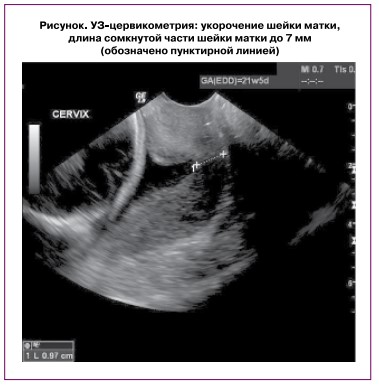

По данным клинико-лабораторных методов верифицировано выраженное укорочение шейки матки до 7 мм (рисунок) с воронкообразным расширением области внутреннего зева, что отражало данные физикального обследования (см. выше).